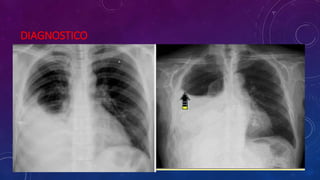

DIAGNOSTICO

ADICIONAL